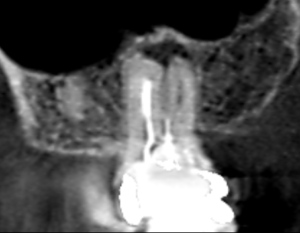

上顎大臼歯の頬側根の矢状断のCT画像です。

赤い矢印の先に膿の影がみられます。

青い矢印の先は、遠心頬側根の未治療の根管です。